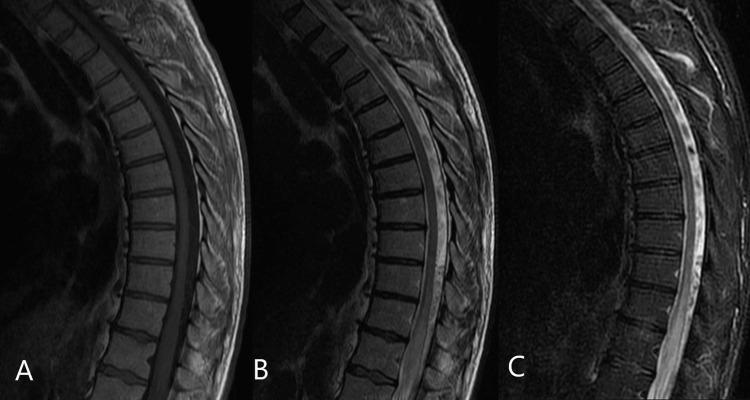

Spinal Dural Arteriovenous Fistula (SDAVF) is a rare and complex vascular condition with significant neurological consequences if left untreated. We present a case of SDAVF in a 46-year-old male who presented with progressive myelopathy. The patient presented with a three-month history of progressive lower extremity weakness, numbness, urinary retention, constipation, and gait disturbance. The spine's magnetic resonance imaging (MRI) showed diffuse T2 hyperintensity and contrast enhancement from T11 to L1, raising the suspicion of an intradural spinal cord lesion. Further evaluation with spinal angiography revealed an SDAVF at the level of T11-T12. The patient underwent surgical resection of the fistula, His lower extremity weakness and numbness improved significantly after surgery, and he was discharged with a plan for close follow-up. Early diagnosis and appropriate treatment prevent neurological deficits and improve patient outcomes. Surgical resection of the fistula can significantly improve neurological symptoms and should be considered a treatment option for SDAVF.

脊髓硬脊膜动静脉瘘(SDAVF)是一种罕见且复杂的血管疾病,如果不进行治疗会产生严重的神经后果。我们报告一例46岁男性的SDAVF病例,该患者表现为进行性脊髓病。患者有三个月进行性下肢无力、麻木、尿潴留、便秘和步态障碍的病史。脊柱磁共振成像(MRI)显示从T11到L1弥漫性T2高信号和强化,怀疑存在硬脊膜内脊髓病变。进一步的脊髓血管造影评估显示在T11 - T12水平存在SDAVF。患者接受了瘘管的手术切除,术后其下肢无力和麻木明显改善,出院时计划进行密切随访。早期诊断和适当治疗可预防神经功能缺损并改善患者预后。瘘管的手术切除可显著改善神经症状,应被视为SDAVF的一种治疗选择。